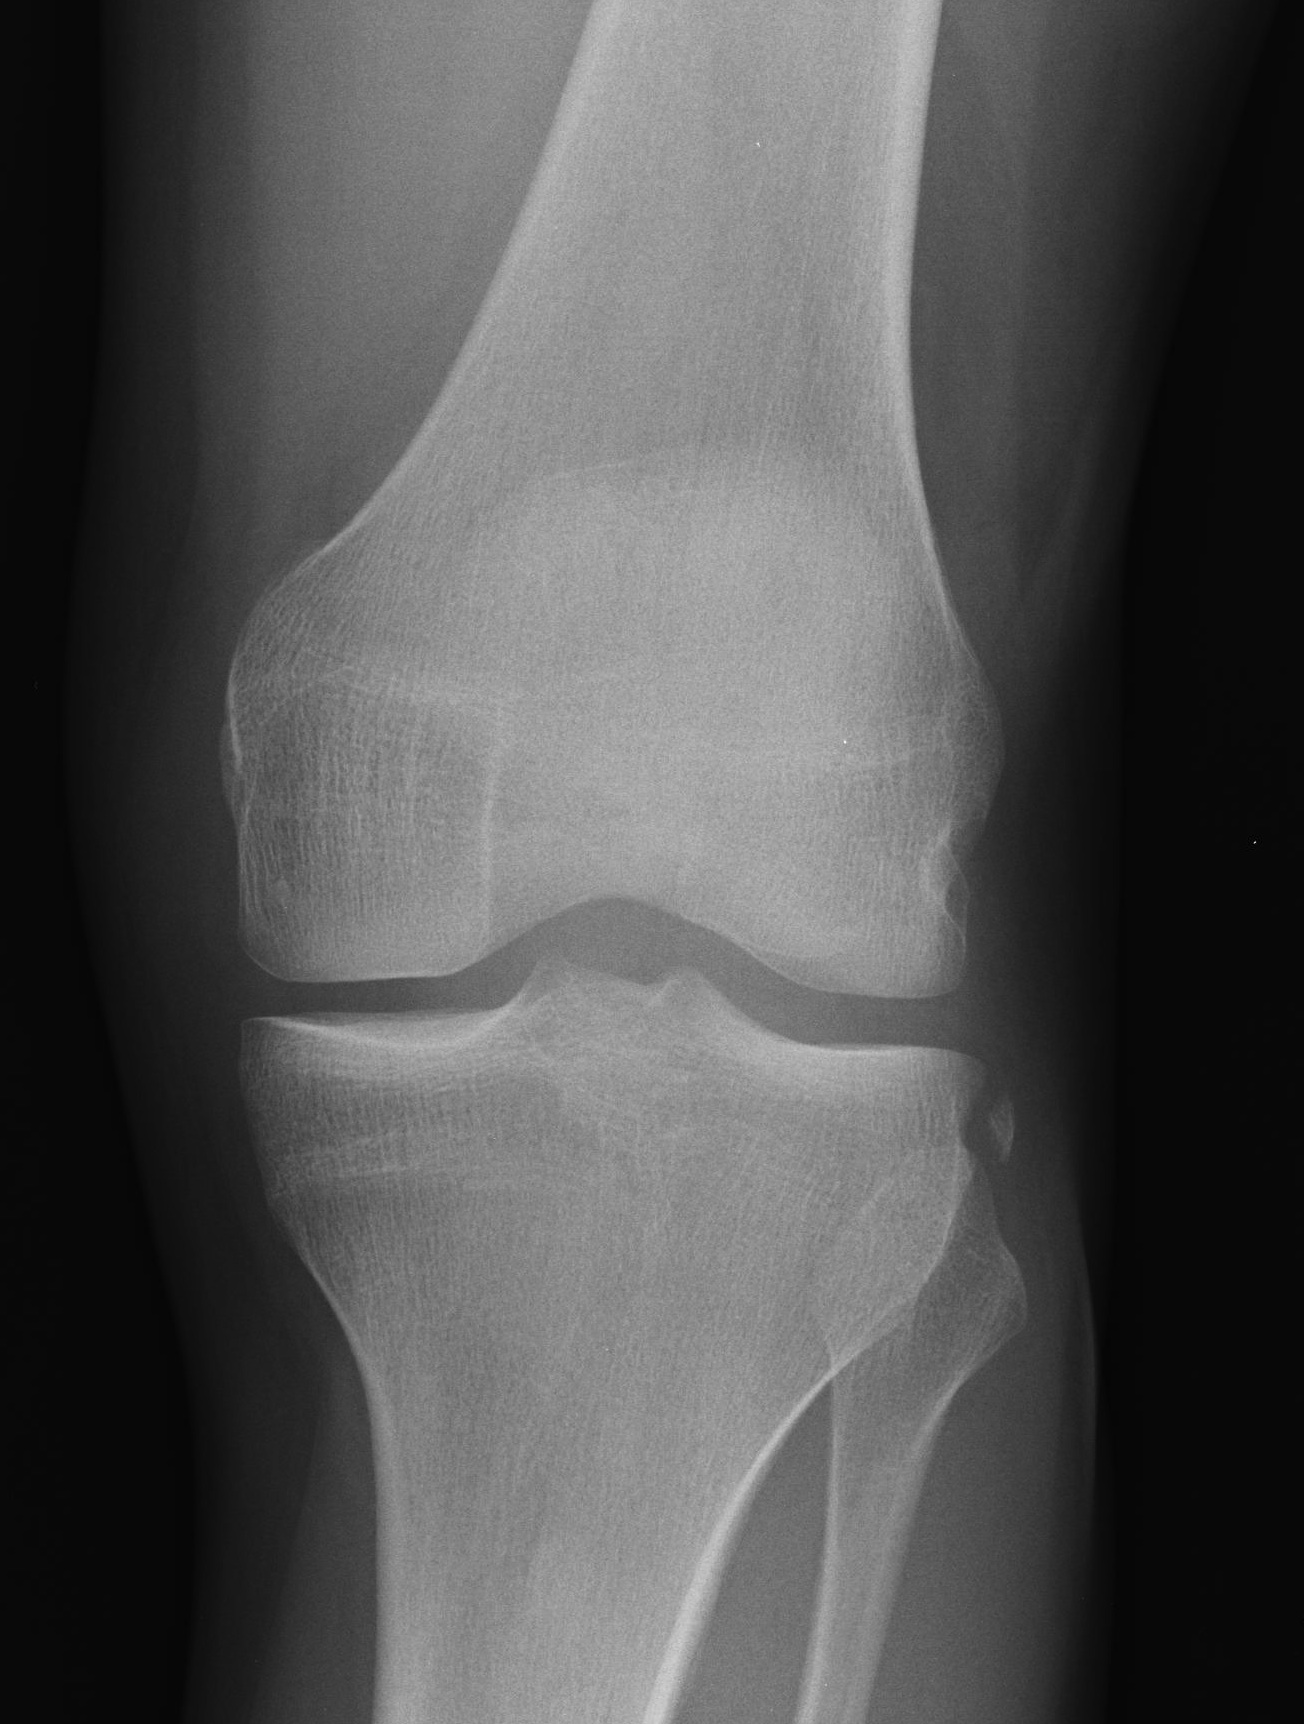

X-ray

Usually normal

Segond Fracture

- small avulsion fracture of lateral proxima tibia

- is sign of lateral capsular avulsion

- pathognomonic of ACL tear

Tibial avulsion

- more common in children

- can be seen in adults